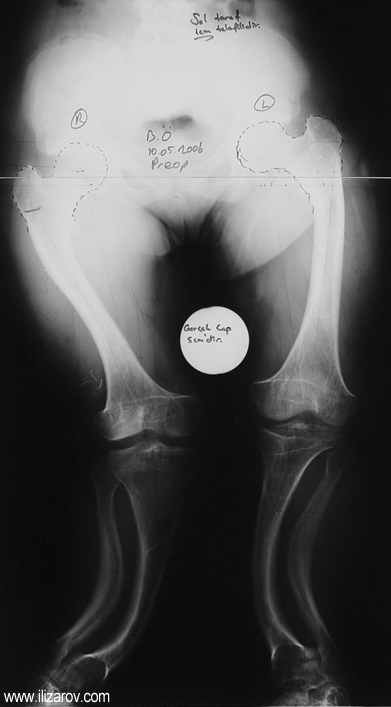

Hipofosfatemik raşitizmde anormal kemik bulguları 1 yaşından sonra belirginleşir; kısa boy ve sıklıkla diz çevresinde deformiteler (bilateral genu valgum ya da varum, tibial torsiyon, femur ve tibiada eğrilik, ‘windswept’ deformitesi) ortaya çıkar.

Vaka 2